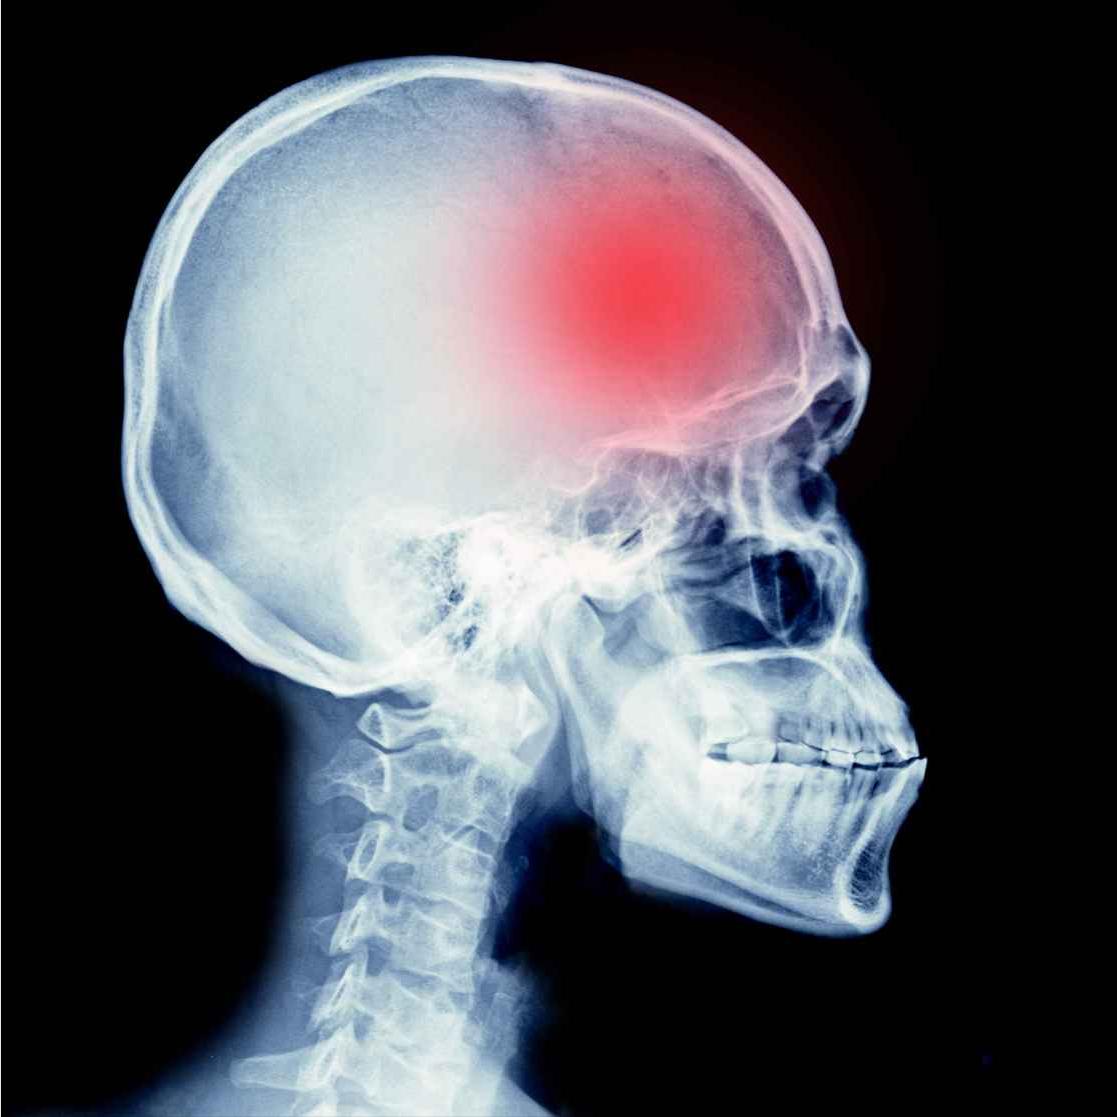

6个突然出现,是脑血栓的最后警告! 脑血栓发生前,身体往往会发出明确的求救信号。如果出现以下6种"突然"症状,请立即就医: 1.突然一侧肢体失控 当一侧手脚突然麻木无力,走路时腿脚拖沓,同侧手臂握不住东西,连写字都变得困难时,这极可能是运动功能区血管发生了堵塞。很多患者事后回忆都会感慨:"那天早上起床,突然发现右手不听使唤了。" 2.突然视力骤变 单眼或双眼突然视物模糊、视野缺损,甚至短暂失明,哪怕几分钟后自行恢复,也决不能掉以轻心。这是眼动脉或大脑视觉通路血供不足的危险信号。 3.突然炸裂样头痛 毫无征兆的剧烈头痛,感觉头部像要炸开一样,程度远超普通头痛。患者常描述"这辈子从没这么痛过",这往往预示着脑血管出现了严重问题。 4.突然天旋地转 突发剧烈眩晕,感觉周围景物都在旋转,同时伴有行走不稳、手脚不协调。想要走路却迈不开腿,想伸手取物却控制不住动作,这可能是小脑或脑干血供出现障碍。 5.突然言语障碍 突然说话含糊不清,舌根发硬,或是完全无法表达。有的患者心里明白,却说不出来,这是大脑语言中枢缺血的典型表现。 6.突然意识混乱 突然不认识家人,找不到回家的路,或是记忆出现混乱,面对熟悉物品却叫不出名字。这些认知功能障碍说明大脑高级功能区域正在缺血。